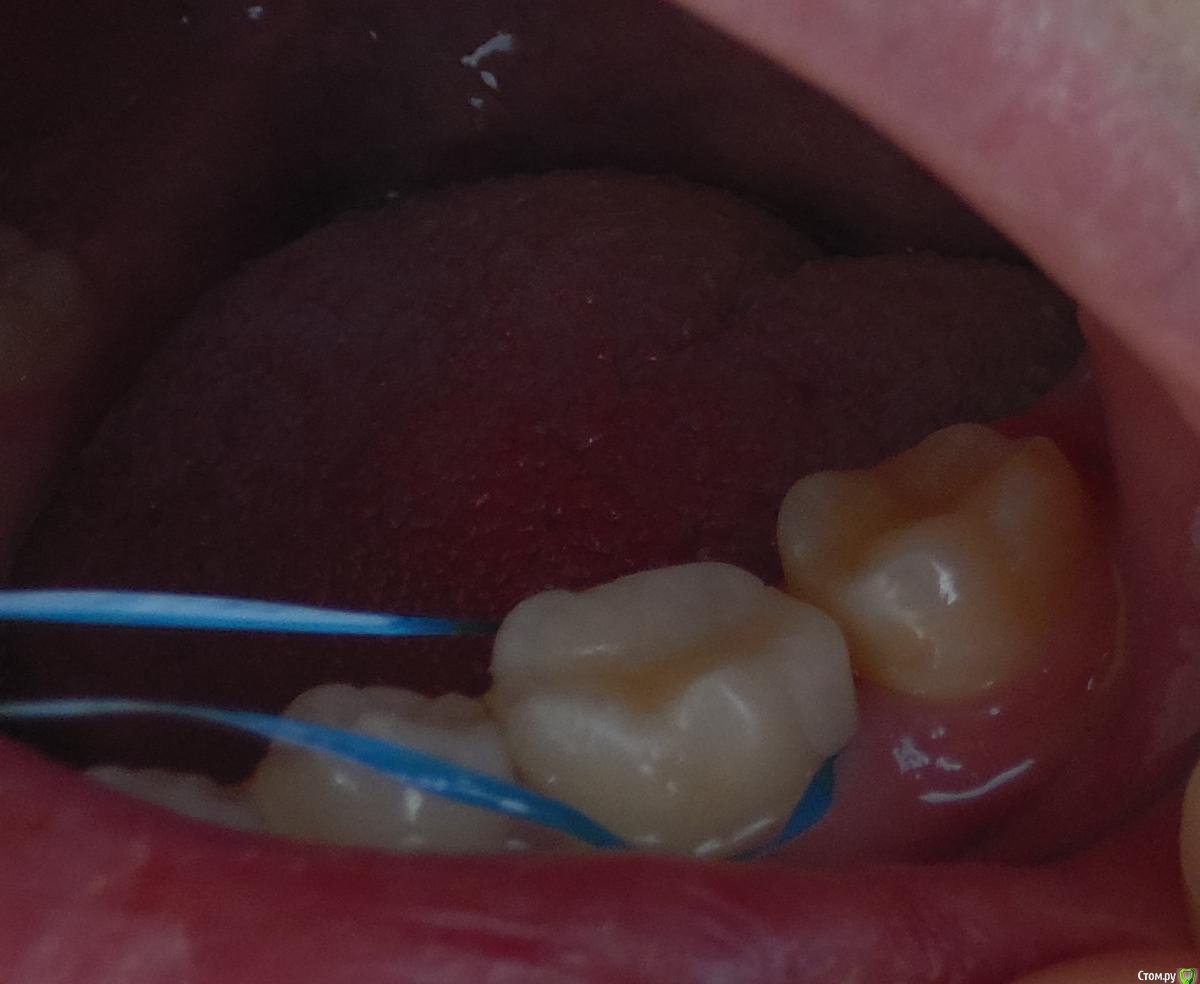

Антон999 Опубликовано 21 ноября, 2017 Поделиться Опубликовано 21 ноября, 2017 Здравствуйте, у меня был контактный кариес на нижней шестерке, зуб депульпировали, штифт не ставили, запломбировали свыше ½ зуба композитом светового отверждения, через неделю произошел маленький скол пломбы в районе контактного пункта, я пришел, мне запломбировали полость скола световой пломбой, но при первом же приеме пищи, эта маленькая пломба отвалилась от большой, я обратился еще раз и мне высверлили часть пломбы (но не всю) и уже большим куском налепили пломбу на пломбу, но теперь у меня не плотный контактный пункт, попадает пища, и под эту “вторую” пломбу заходит зубная нить (фото) и пища попадает под пломбу, с помощью объемной нити вычищаю под ней, но мне кажется она со временем отвалиться. Скажите пожалуйста нужно ли мне опять все переделывать? Допустимо ли удалять часть пломбы, а не всю, и крепить новую? В коронковой части зуба, только половина своих стенок, нечего страшного, что штифтом не укрепили? И заодно посмотрите пожалуйста качественно ли мне запломбировали три канала в этом зубе, спасибо. Ссылка на комментарий